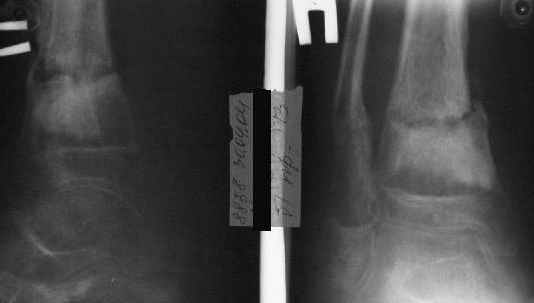

Есть даже тень периостальной костной мозоли и сросшийся перелом

малоберцовой кости.

Это сросшийся перелом малоберцовой кости. И ложный сустав

н\3 б\берцовой кости.

Так как речь зашла непосредственно о травме, см этапные

снимки. Как все было

Первичные

Вытяжение

Фиксация

в гипсе

Промежуточный